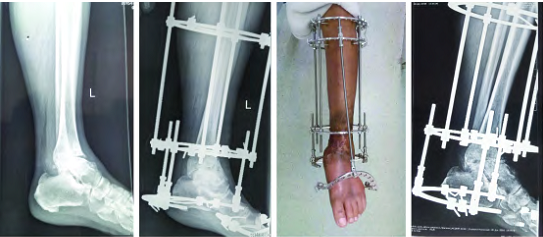

踝关节开放性损伤伴感染 3 年,感染控制后 6 个月行踝关节融合术

Ilizarov 外固定架主要应用于合并复杂畸形或软组织条件不良的严重足踝病变,在融合的同时,可以矫正畸形,在临床上应用较广。